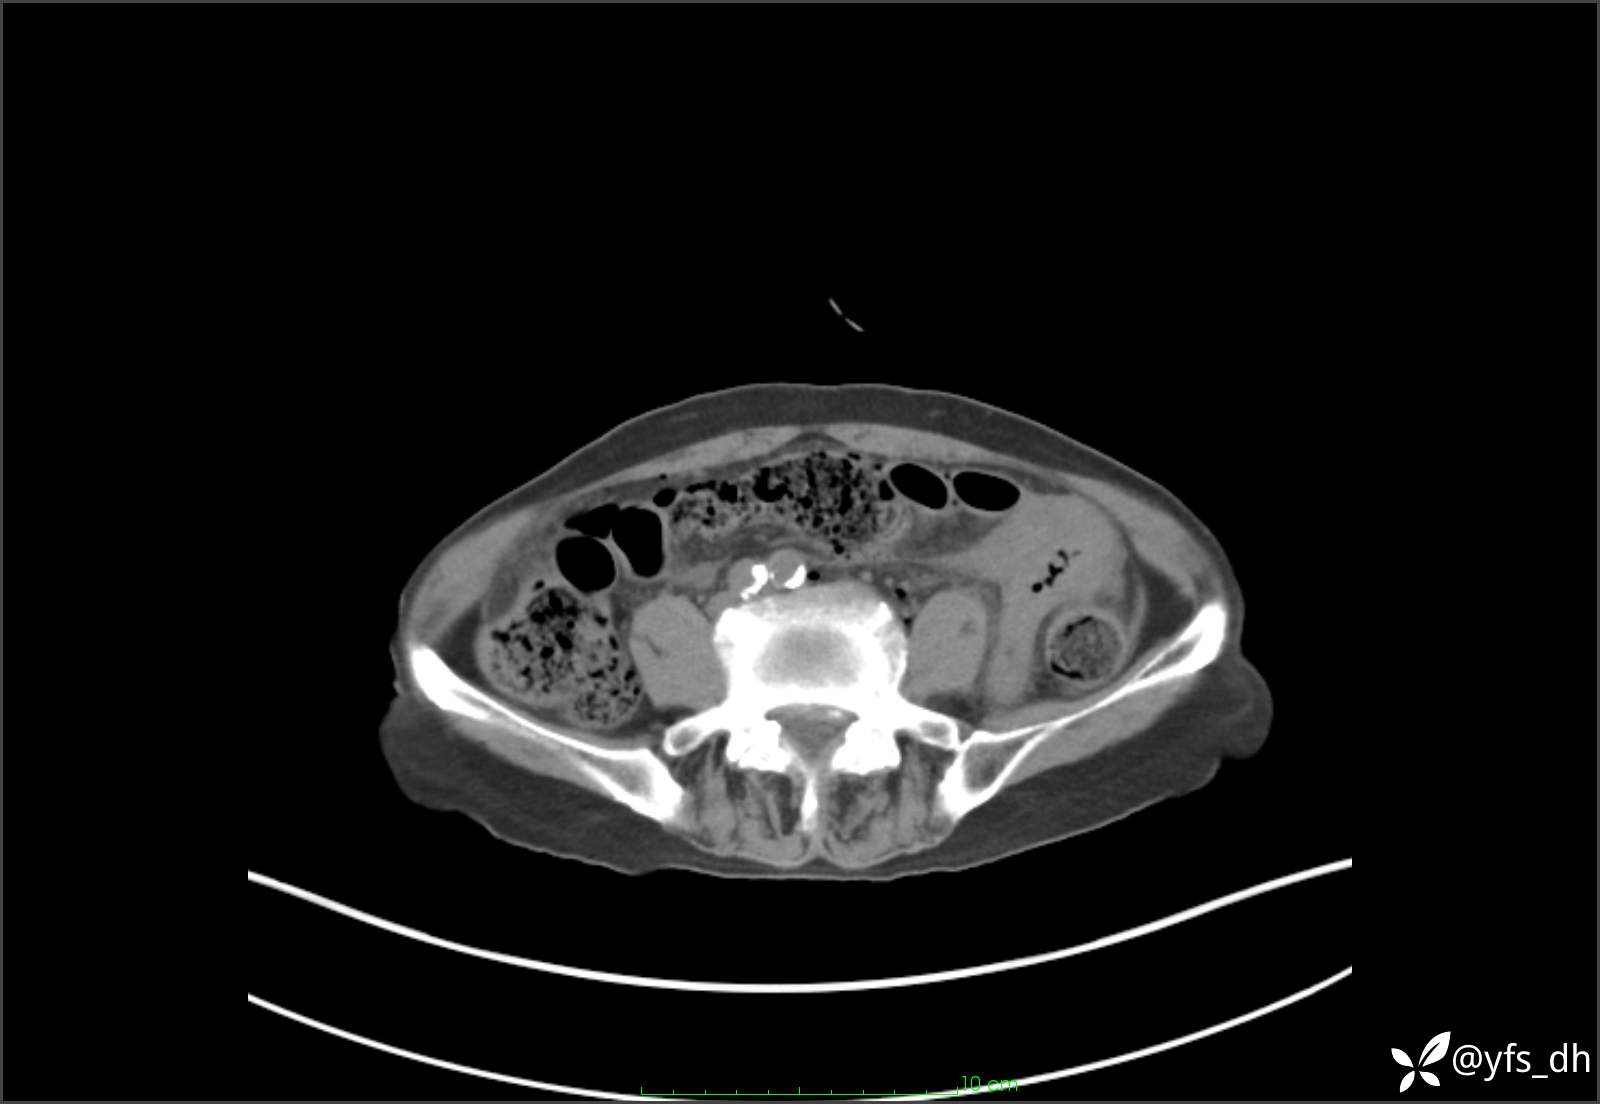

1.简要病史:患者4天前突发上腹部疼痛不适,但可以忍受。3小时前饭后突然加重,不能忍受后就诊。

2.简要手术记录:术中见腹盆腔大量肠液及粪便,乙状结肠中下段见一约3cm的破口。